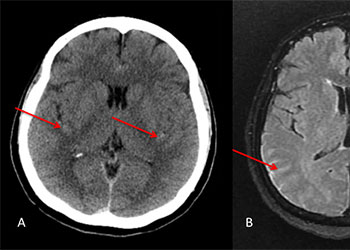

Brain:

74 Year Old Woman with Occipital Headaches

Author: Michael Brisman M.D., F.A.C.S., Read More!